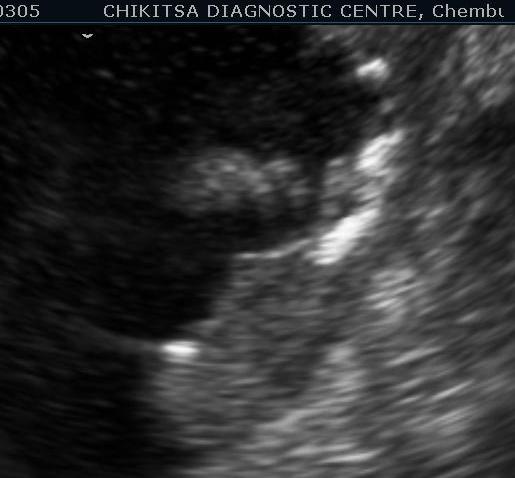

5 5 cm x 5 cm size  ill-defined heterogeneous area in the posterior wall of the urinary bladder which is thickened and measures upto 0.6 cm in thickness. Large solid calcific areas are noted in the thicknened portion of the wall urinary bladder.  Suggestive of schistosomiasis of the  urinary bladder (possibly with malignant change).

Lesion in the wall of the urinary bladder has increased in size. Calcific areas are noted. Urinary bladder malignancy ( confirmed by histopathology), possibly following schistosomiasis.